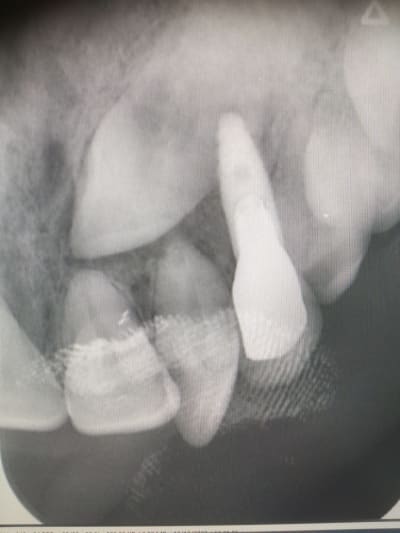

@ Hokusai

Là aussi on est très proche. Trop d'ailleurs.

Ca s'est mal terminé.

Je me souviens d'une conf à l'ADF d'un praticien qui affirmait avec beaucoup d'aplomb qu'il n'y avait aucun problème à transfixer des racines. Depuis j'ai vu ce cas, et j'ai un peu plus de doutes.

C’était juste un peu d’inquiétude de ma part comme je voyais un peu d’interrogation chez mon dentiste que le bout de la racine soit entre 0,5mm et 1mm de l’implant, j’essayais de me rassurer en me disant que la racine était dévitalisée et je pensais donc que ça pouvait marcher sans devoir tout recommencer 😔